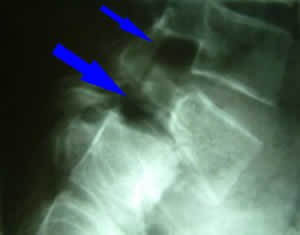

Лечението на дискова херния може да бъде консервативно или хирургично. В консервативното лечение се използват нестероидни противовъзпалителни лекарства, аналгетици, физиотерапия, балнеолечение, ЛФК, озон терапия и акупунктура. Освен това се споменават хомеопатични инжекции Discus Compositum и лечение с протеолитични ензими. Оперативното лечение се предлага при тежки случаи, когато консервативните методи не доведат до подобрение. Консервативните лечения за дискова херния включват използването на нестероидни противовъзпалителни лекарства, обезболяващи, физиотерапия, балнеолечение, ЛФК, озон терапия и акупунктура. Освен това се споменават хомеопатични инжекции Discus Compositum и лечение с протеолитични ензими. Потребителите споделят различни методи за лечение на дискова херния, включително мануална терапия, физиотерапия, инжекции и хомеопатично лечение. Препоръчително е цялостно лечение и консултация със специалисти.